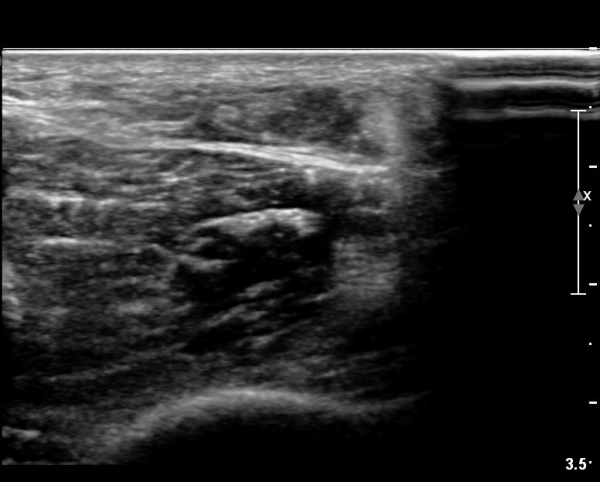

[¹ß¸ñ] simultaneosus tear of GCM and achiles tendon

abrupt leg pain developed during foot volleyball

he walk with severe limping with no weight bearing on rt. leg. on examination, there is local tendernes at GCM and achiles tendon, severe pain with ankle dorsiflexion.

ÃÊÀ½ÆÄ °Ë»ç

rec) short leg splint with crutch gait. he refused splint, then visit other hospital and took operation.